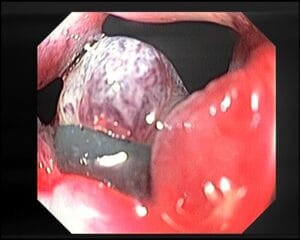

LIGADURA DE HEMORROIDES CON BANDAS

La ligadura de hemorroides con bandas es un procedimiento ambulatorio utilizado para tratar las hemorroides, que son dilataciones de los vasos sanguíneos en el área...